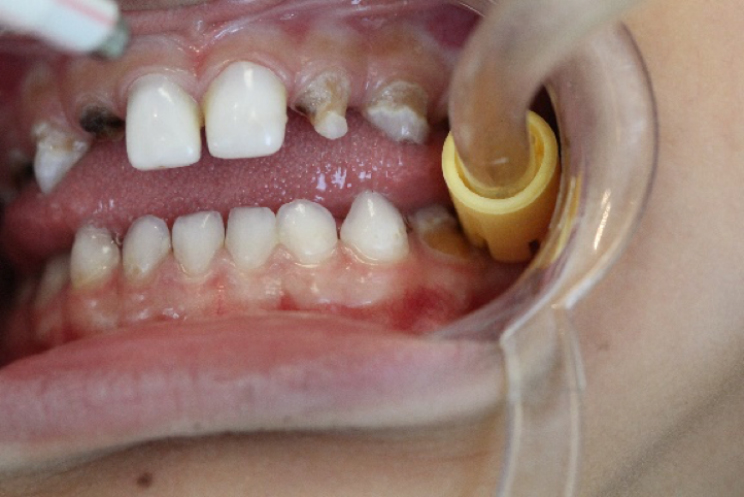

Em seguida realizou-se o isolamento relativo com rolete de algodão e secagem dos elementos com jato de ar. Foi realizada barreira gengival e fotopolimerização da mesma. (foto 7, 8 e 9)